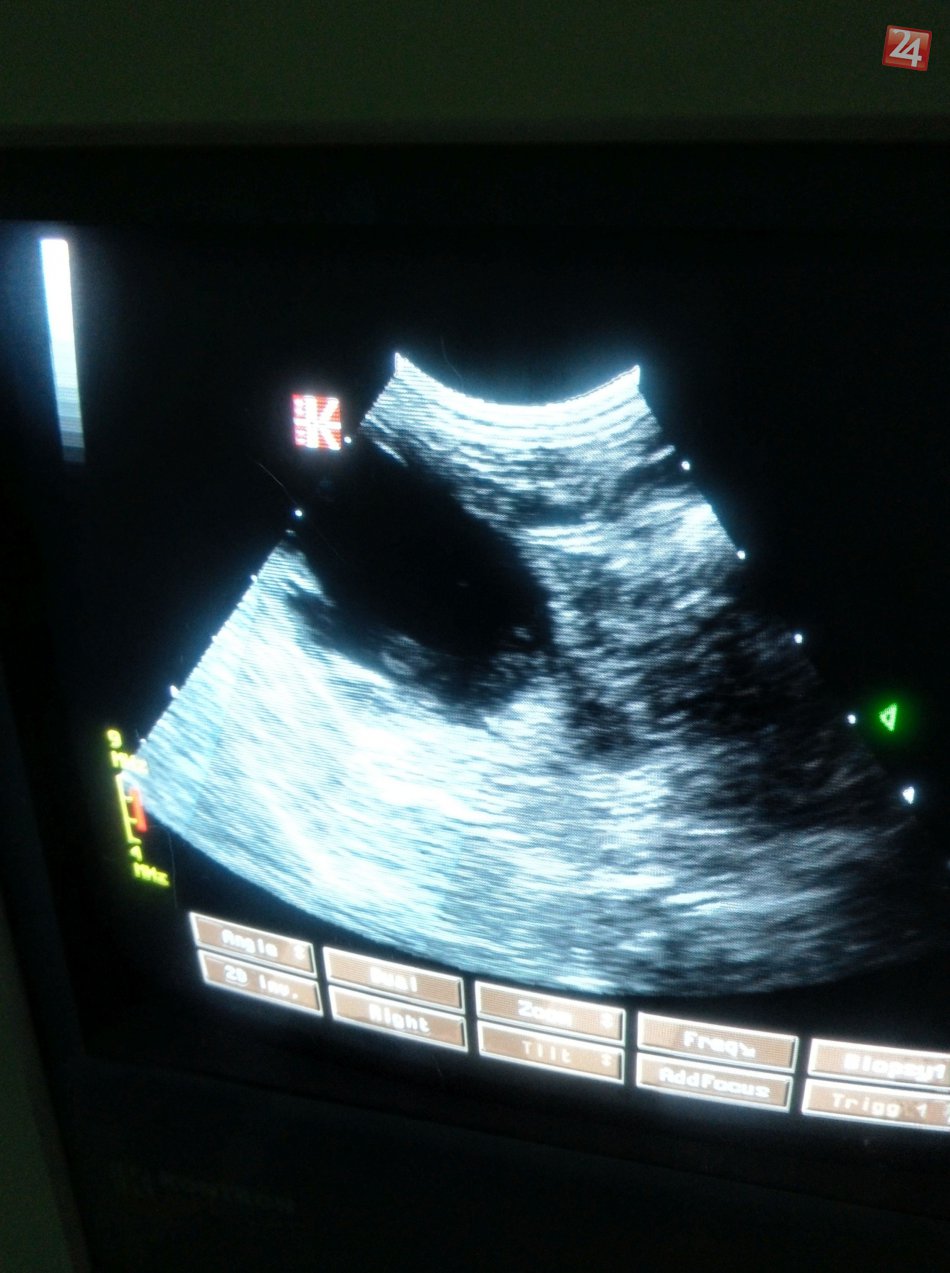

Galéria k článku Obľúbené veterinárne duo z Bystrice: Mama so synom zasvätili život pomoci nemým tvorom